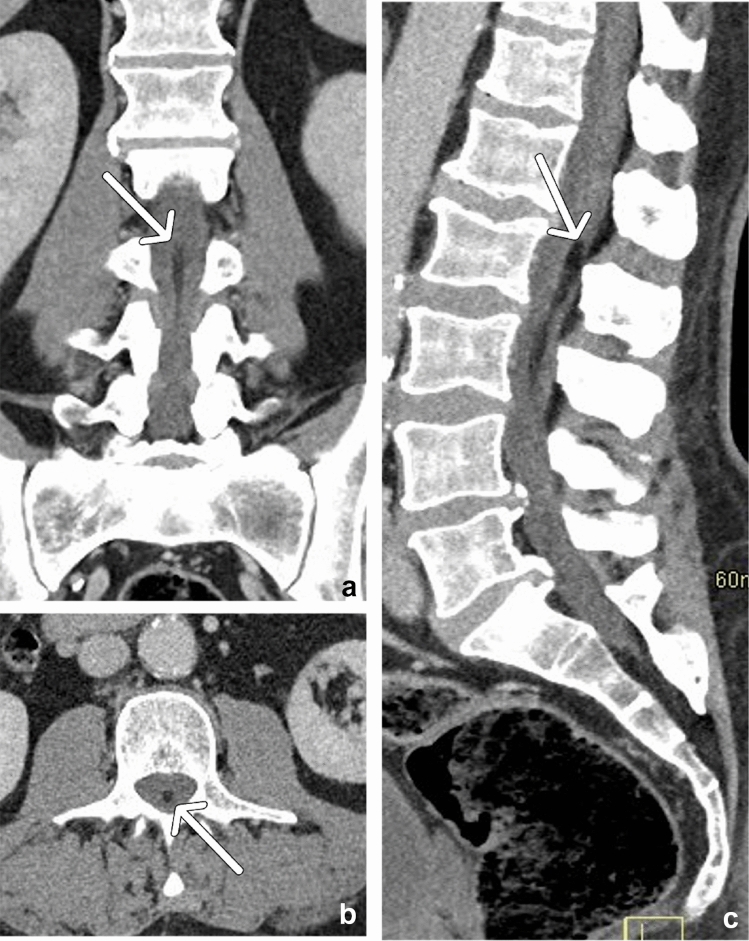

Fig. 11.

63-year-old male with a filum terminale lipoma. Coronal (a), axial (b), and sagittal (c) CT reformats demonstrate a linear region of fat attenuation (arrows) at the base of the conus medullaris extending from L2 to L3, along the filum terminale, representing a filum terminale lipoma. The patient had no clinical signs of tethered cord syndrome

Filum terminale lipoma

The filum terminale is a fibrous strand of primarily pia mater, which extends from the conus medullaris (usually located at L1) to the periosteum of the coccyx and provides longitudinal support for the distal spinal cord. A filum terminale lipoma, also known as fatty filum terminale, is a common incidental finding in the lumbar spine, present in up to 4–6% of post-mortem exams [18], and is usually of no clinical concern; however, there may be an association with tethered cord syndrome. On CT imaging, a filum terminale lipoma will be seen as a fat density, linear, low-attenuating mass below the level of the conus medullaris (Fig. 11). MRI should be recommended if there are clinical signs of tethered cord. On MRI, the filum terminale lipoma will follow fat signal intensity on all sequences. Associated findings in support of tethered cord syndrome include filum thickening (> 2 mm) and a low-lying conus, at or below the midpoint of L2 [19–21].